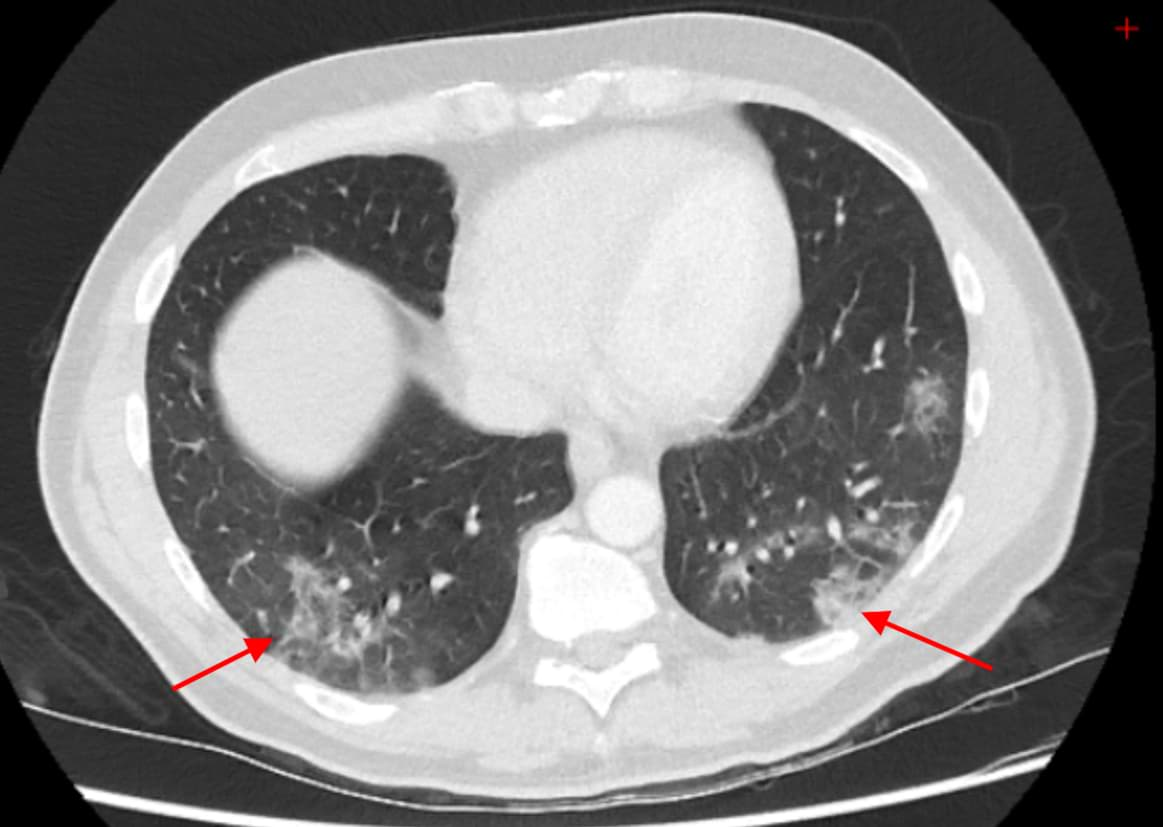

Obligatory features:

- Ground-glass opacities, with or without consolidations, in lung regions close to visceral pleural surfaces, including the fissures (subpleural sparing is allowed) AND

- Multifocal bilateral distribution

Confirmatory patterns:

- Ground-glass regions

- Unsharp demarcation, (half) rounded shape.

- Sharp demarcation, outlining the shape of multiple adjacent secondary.

- Pulmonary lobules.

- Crazy paving.

- Patterns compatible with organizing pneumonia.

- Thickened vessels within parenchymal abnormalities found in all confirmatory patterns.